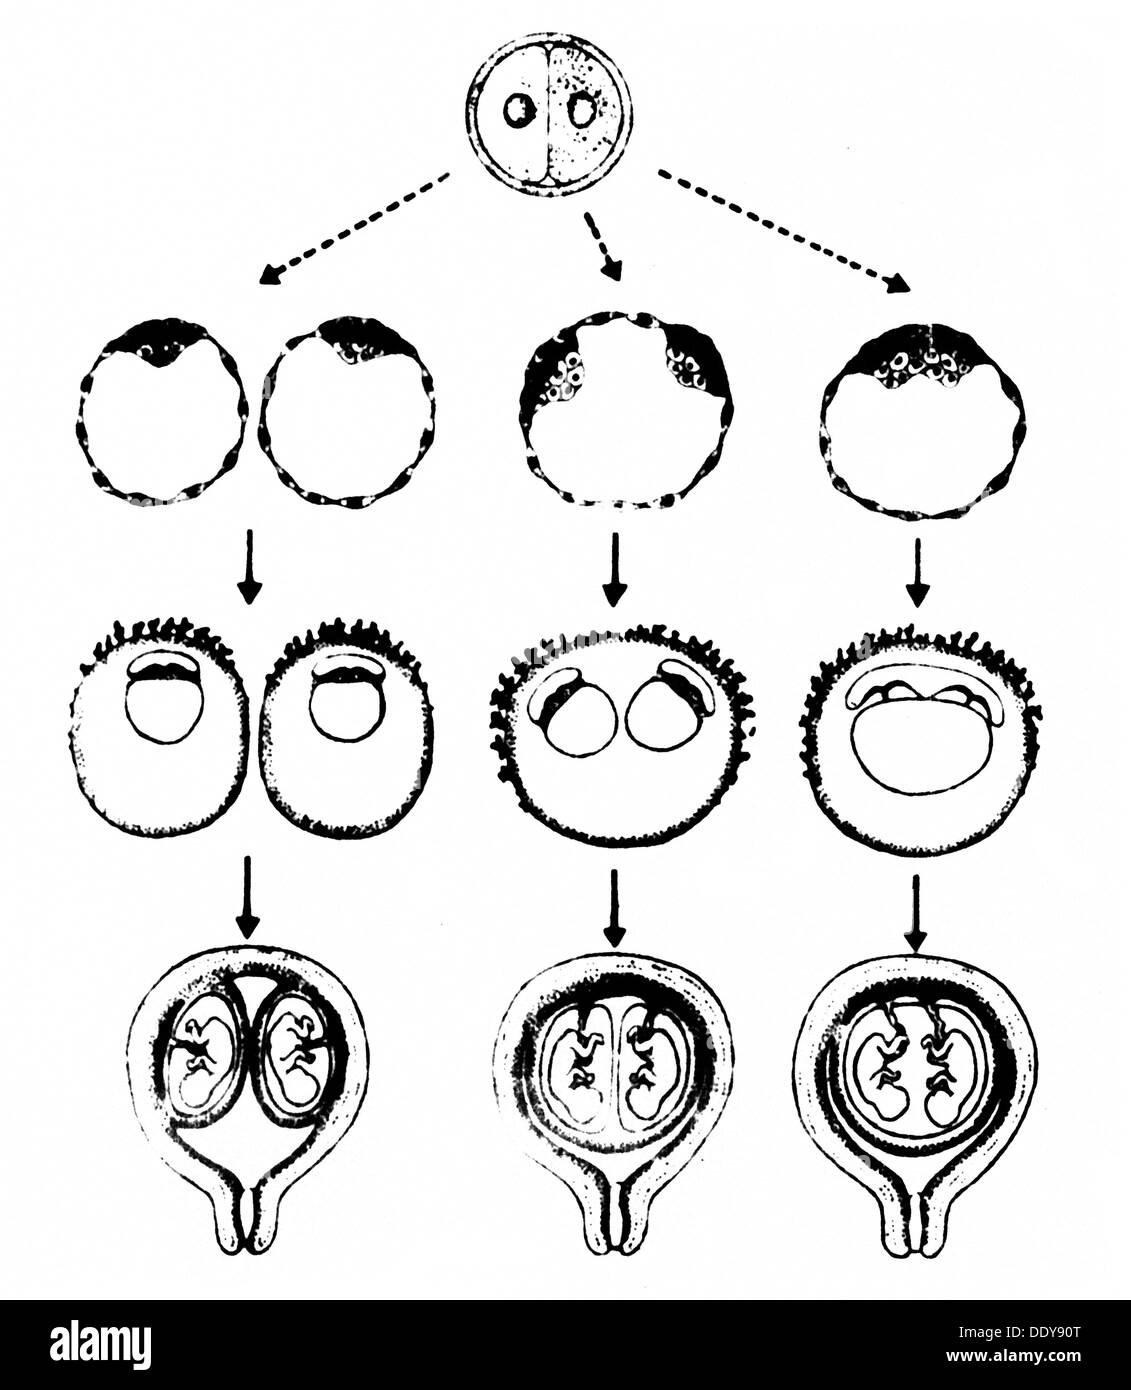

Personnes, jumeaux, schéma du développement possible de jumeaux monozygotes, dessin, de: 'Zeitschrift für Klinische Medizin', 42. Volume, numéro 10, 1987, droits additionnels-Clearences-non disponible Banque D'Imageshttps://www.alamyimages.fr/image-license-details/?v=1https://www.alamyimages.fr/personnes-jumeaux-schema-du-developpement-possible-de-jumeaux-monozygotes-dessin-de-zeitschrift-fur-klinische-medizin-42-volume-numero-10-1987-droits-additionnels-clearences-non-disponible-image60221416.html

Personnes, jumeaux, schéma du développement possible de jumeaux monozygotes, dessin, de: 'Zeitschrift für Klinische Medizin', 42. Volume, numéro 10, 1987, droits additionnels-Clearences-non disponible Banque D'Imageshttps://www.alamyimages.fr/image-license-details/?v=1https://www.alamyimages.fr/personnes-jumeaux-schema-du-developpement-possible-de-jumeaux-monozygotes-dessin-de-zeitschrift-fur-klinische-medizin-42-volume-numero-10-1987-droits-additionnels-clearences-non-disponible-image60221416.htmlRMDDY90T–Personnes, jumeaux, schéma du développement possible de jumeaux monozygotes, dessin, de: 'Zeitschrift für Klinische Medizin', 42. Volume, numéro 10, 1987, droits additionnels-Clearences-non disponible